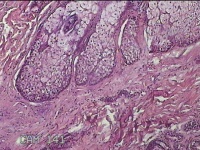

右侧颜面部结节

性别

男

年龄

49岁

临床诊断

皮脂腺囊肿

一般病史

发现右侧颜面部结节5年余。

标本名称

大体所见

灰白暗红色组织1x0.7x0.3cm一块,表面带梭形皮肤1x0.5cm,皮下见结节0.9x0.7x0.3cm一个,切开结节呈实性,切面灰白暗红色,质中。

图3